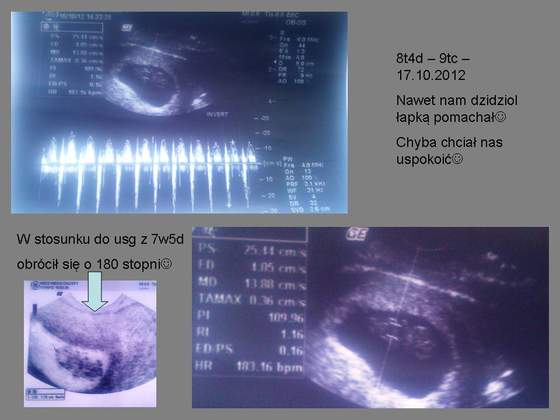

Ból powoli zaczął się zmniejszać, na 15 wczoraj pojechałam do gin, okazało się że z maluchem wszystko w porzadku, ale odetchnęłam, bardzo się bałam!

nawet rączką nam pomachał!

8t4d.jpg8t4d_16102012.jpg8t4d_16102012a.jpg